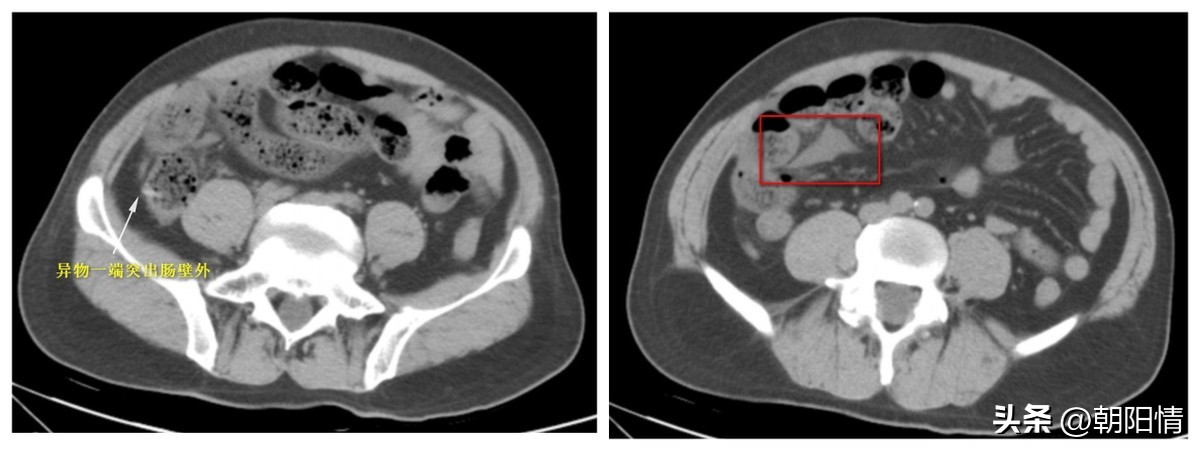

Case7:男性,54岁,下腹部绞痛入院,行下腹部CT平扫。手术证实:小肠异物并穿孔(鸡骨头);腹腔积液、积脓。

Case8:老年女性,突发腹痛就诊。腹部CT示:小肠异物合并肠梗阻。患者灌肠治疗见大量冬菇。